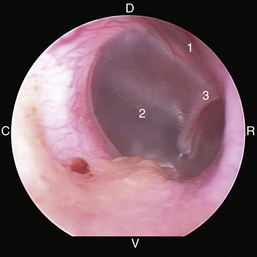

image

Figure 20-8 Normal canine tympanic membrane of the left ear. 1, Pars flaccida; 2, pars tensa; 3, stria mallearis; 4, bulla septum; C, caudal; D, dorsal; R, rostral; V, ventral.

(Courtesy of Dr. Lynette Cole, The Ohio State University, Columbus, Ohio.)